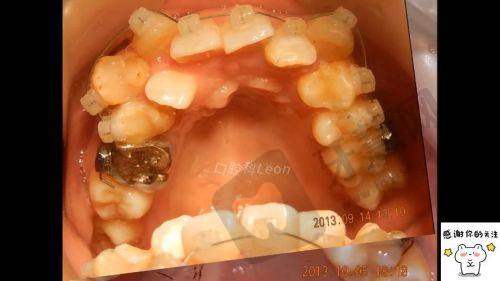

保定北京儿童医院在矫正牙齿方面口碑良好,擅长门牙前突矫正、3M金属托槽牙套矫正、牙齿歪斜矫正、龅牙矫正、拔牙即刻矫正、牙根突出矫正、牙骨突出矫正等项目。推荐的医生有程睿达、康锐思、刘彭。

保定北京儿童医院正畸医生介绍1、程睿达:女,从业8余年,保定北京儿童医院正畸主丨任医师。擅长骨性深覆合正畸、牙根突出矫正、大学生牙齿矫正、陶瓷牙套矫正。

2、康锐思:男,从业10余年,保定北京儿童医院正畸主治医师,擅长正雅悦享版牙套矫正、固定矫治器矫正牙齿、牙齿拥挤矫正、咬合垫牙齿矫正。

保定北京儿童医院矫正牙齿价格:低7707元起

牙骨突出矫正7707元起;

门牙前突矫正8963元起;

牙根突出矫正10419元起;

3M金属托槽牙套矫正9887元起;

隐适美完整套装牙套矫正11545元起;

牙齿歪斜矫正11541元起;

双颌前突矫正9341元起;

龅牙矫正11444元起;

陶瓷托槽牙齿矫正8268元起;

拔牙即刻矫正11321元起;